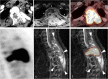

Results: Sixteen of the 21 cases were benign and 5 were aggressive OBs. Tumors were located in the lumbar (n = 11), cervical (n = 4), thoracic (n = 5), and sacral (n = 1) spinal regions. Nineteen cases were centered in the posterior elements of the spine, 13 of which extended into the vertebral body. Punctate or nodular calcifications were found in all cases on CT with a complete sclerotic rim (n = 12) or incomplete sclerotic rim (n = 8). The flare phenomenon (indicative of surrounding tissue inflammation) was found in 17/21 cases on CT, thin in 11 cases and thick in 6 cases, and in 19/19 cases on MRI, thin in 1 case and thick in 18 cases. On 18F-FDG PET/CT, all cases (8/8) were metabolically active with the SUVmax of 12.3-16.0; the flare sign was observed in 8 cases, including 7 cases of hypometabolism and 1 case of coexistence of hypermetabolism and hypometabolism. Based on CT, 3, 12, and 6 cases were classified as Enneking stage 1, 2 and 3, respectively. Of 19 cases with MRI, 1 and 18 cases were classified as Enneking stage 2 and 3, respectively.